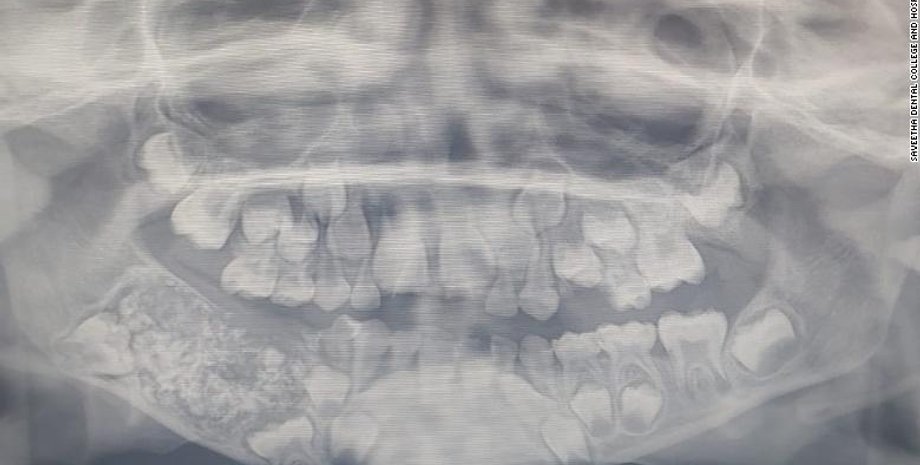

Рентген челюсти ребенка. Фото: Saveetha Dental College and Hospital

Мальчик был госпитализирован в южном городе Ченнаи из-за отека и болей в нижней челюсти. На рентгене врачи увидели в нижней челюсти мальчика мешок, заполненный недоразвитыми зубами.

Команде хирургов понадобилось около 5 часов, чтобы достать из челюсти ребенка все "лишние" зубы.

"Всего было 526 зубов, размер которых варьировался в диапазоне от 0,1 мм до 15 мм. Даже у самых маленьких зубов имелся корень и эмаль", – заявила доктор Пратиба Рамани, руководившая операцией.